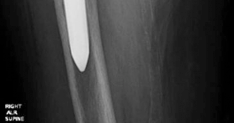

History of presenting complaint : Presents with a draining wound and well-fixed cementless components with a constrained liner due to absent abductor mechanism (Fig. 19.12). Treated with Prostalac and six weeks of IV antibiotics (Fig. 19.13). At the 6-week point, the patient sustained a ground level fall with an acetabular fracture and displacement of the acetabular Prostalac (Fig. 19.14).

Diagnosis : Treated MRSA infection of the right THA with acute acetabular fracture and patient now unable to mobilize due to pain (Fig. 19.14).